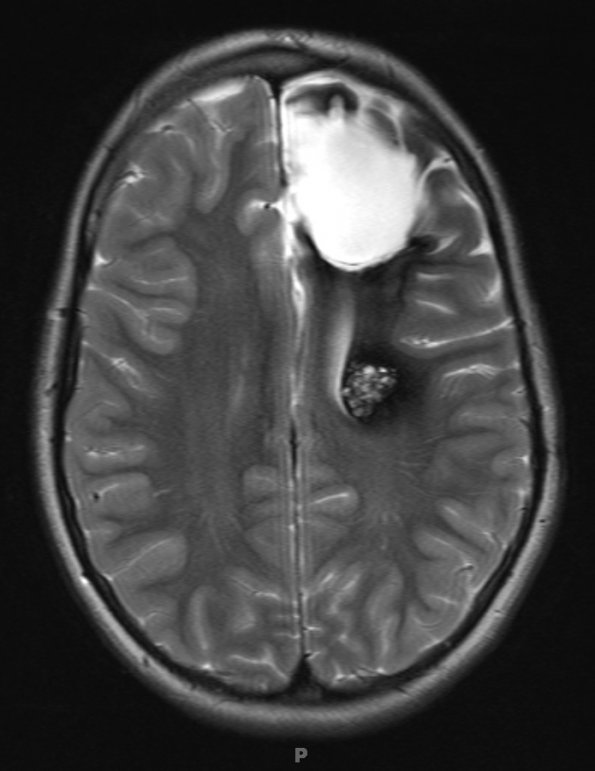

Case 11 History The patient is an eight year old boy with a left frontal cavernoma, one of several. ---- The MRI shown was obtained three years after a previous neurosurgical procedure to remove another CA which had hemorrhaged spontaneously. Operative procedure: Craniotomy for excision of left frontal lesion